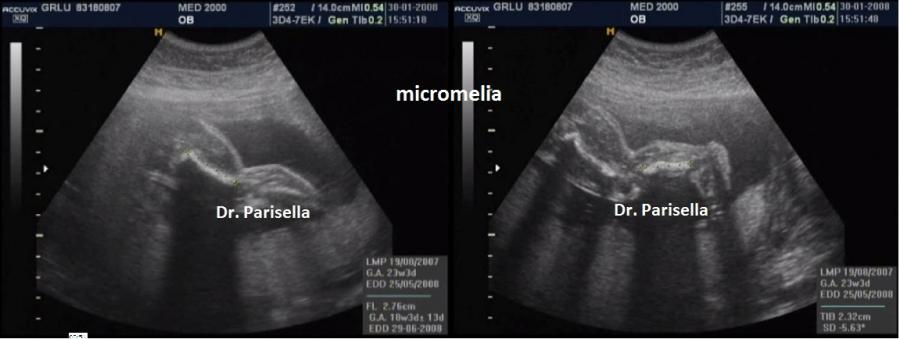

La MICROMELIA SEVERA e l’ IPOPLASIA TORACICA SEVERA (legata al torace stretto con coste corte) sono i segni principali presenti in tutte e quattro i tipi di SRPS e che indirizzano verso una corretta diagnosi. La POLIDATTILIA è presente nei primi due tipi, meno frequentemente nel tipo III, è assente nel tipo IV.

La MICROMELIA SEVERA e l’ IPOPLASIA TORACICA SEVERA (legata al torace stretto con coste corte) sono i segni principali che indirizzano verso una corretta diagnosi. La POLIDATTILIA, sempre presente, è di tipo postassiale ed interessa sia mani che piedi. Spesso è presente idrope.

La MICROMELIA SEVERA e l’ IPOPLASIA TORACICA SEVERA (legata al torace stretto con coste corte) sono i segni principali che indirizzano verso una corretta diagnosi.

1)    Tutte e quattro sono caratterizzate da micromelia severa ed ipoplasia toracica severa.